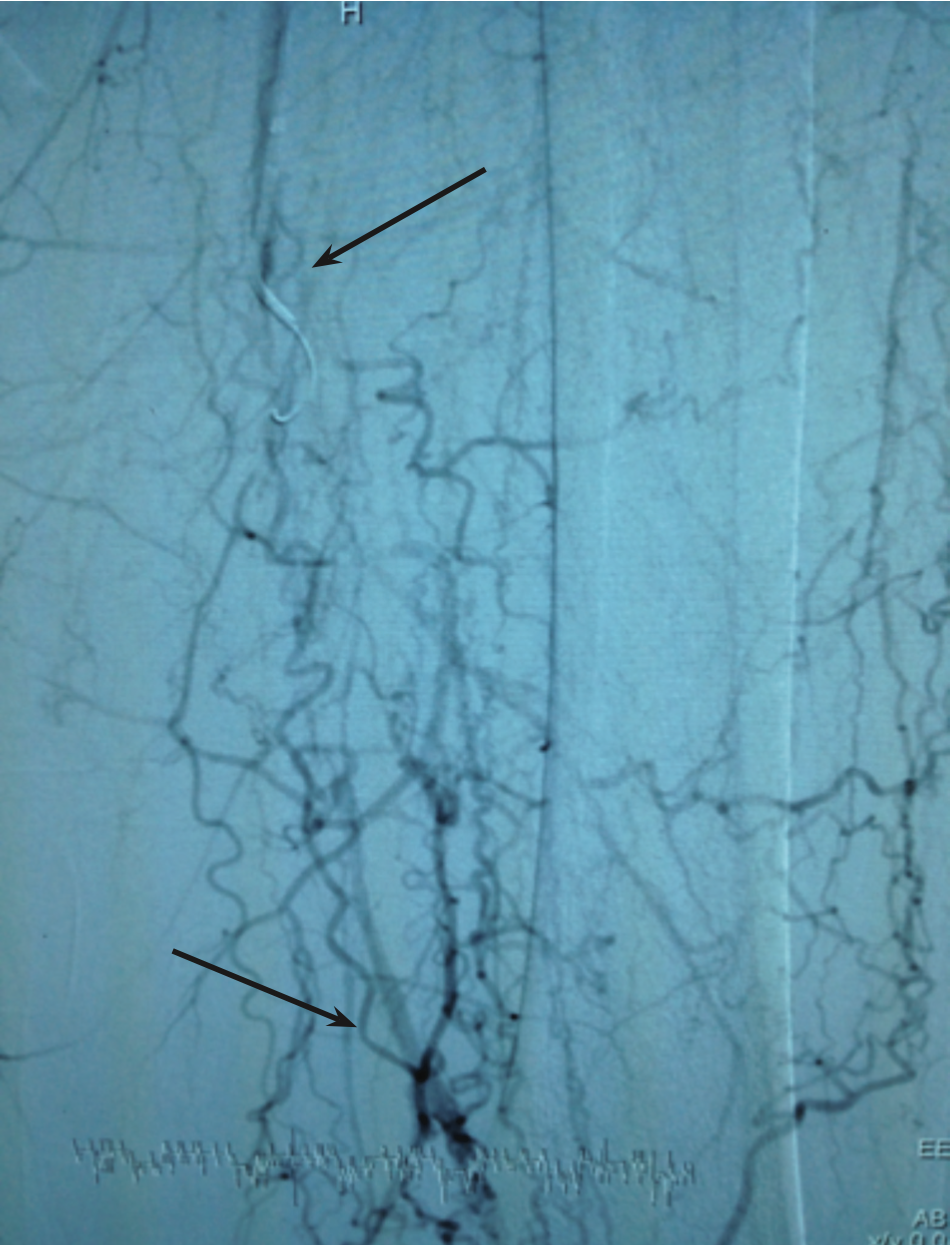

The 5 Fr system was exchanged for a 7 Fr 0.038-inch x 90 cm Flexor Check-Flo Raabe sheath (Cook Medical). Angiography confirmed flush occluded left SFA at its ostium (note arrow in Figure 1). We advanced a 0.035-inch x 260 cm Advantage glidewire with a 5 Fr angled-tip Glide catheter support and crossed half way down the occluded SFA. At this point, we were subintimal and could not advance any further (note upper arrow in Figure 2).

After securing arterial access in the left DP, we attempted to advance the antegrade crossing wire from the right CFA access. We exchanged for a Slip-Cath Beacon Tip DAV catheter (Cook Medical) and advanced an Approach CTO wire (Cook Medical) through this catheter. From the antegrade approach, we were able to position the wire in the distal SFA, but despite our best attempts, the wire was suboptimal for a significant portion. The distal tip of the wire was not in the true lumen of the left popliteal artery, even after exchanging the DAV catheter for a Quick-Cross support catheter (Spectranetics) and then for a CXI Support catheter (Cook Medical). Unsuccessful attempts were also made with a Prowater coronary guide wire (Abbott Vascular).

We then proceeded to work retrograde through the left DP sheath with a CXI Support catheter and wired with a Prowater guide wire. We were able to pass the distal SFA occluded cap, but only partially. The wire was then exchanged for a 0.014-inch x 300 cm Confianza guide wire (Abbott Vascular) with moderate success. We then exchanged for a 0.018-inch x 300 cm Victory 18 (Boston Scientific) control guide wire, which helped us advance to the level of the mid SFA. At this point, we confirmed a short segment of overlap of both the wires. We advanced a Rapid Exchange (RX) 2 mm x 80 mm Amphirion Deep (Medtronic) balloon retrograde from the pedal sheath to the SFA, and performed balloon inflation. Several wire exchanges were performed in order to attempt reentry into the true SFA lumen. Eventually, the left SFA lumen was accessed with a 0.014-inch x 300 cm Runthrough NS (Terumo) from the pedal sheath. The distal tip of the Runthrough NS wire was carefully manipulated into the Flexor Check-Flo Raabe sheath and exteriorized out of the CFA end of the sheath without the use of snares.